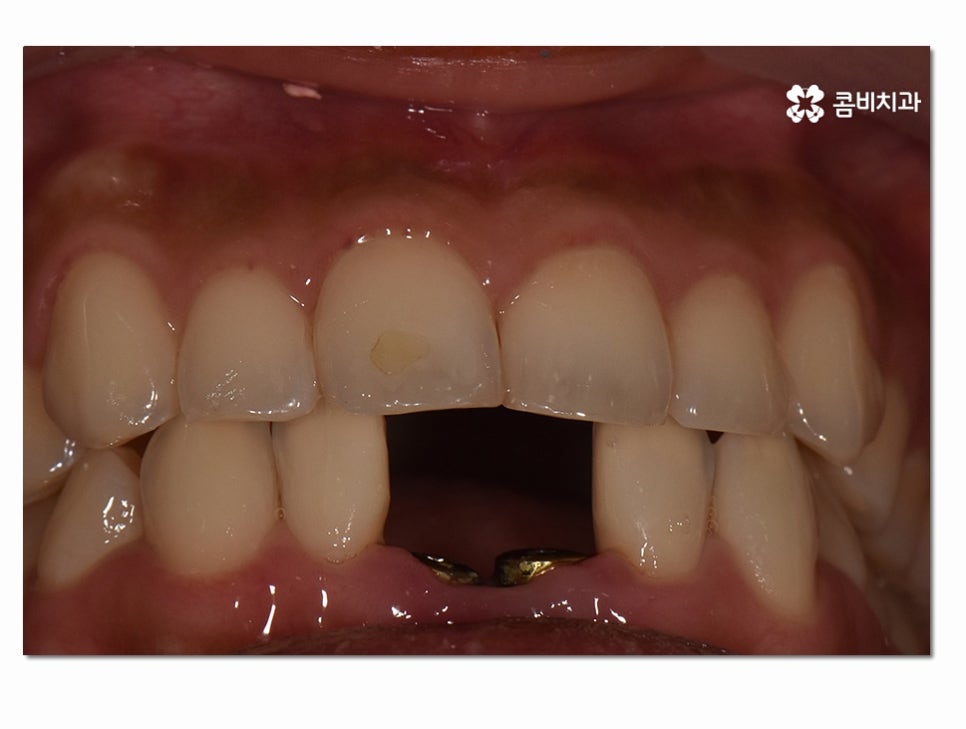

이렇게 인공치근이 골 유착 과정을 거치면 거의 자연치아와

흡사한 씹는 힘을 갖추게 되며 위 환자분과 같이 아랫니 임플란트 위치가

앞니 근처라면 심미적으로 중요한 위치이기 때문에 더 신경 써서

심미성을 회복하는 과정을 거치게 되실 수 있어요.

(좌 - 임플란트 식립 후 임시치아를 부착하고 안전하게 골 유착이 되도록 기다리는 과정, 보철물과 결합 준비 - 우)

인공치근이 튼튼하게 자리를 잡게 된 것이 확인이 되면

보철물을 주변 치아의 색과 모양과 비슷하게 제작하여

결합하는 과정을 거치고 아랫니 임플란트 치료 과정이 마무리될 수 있어요.